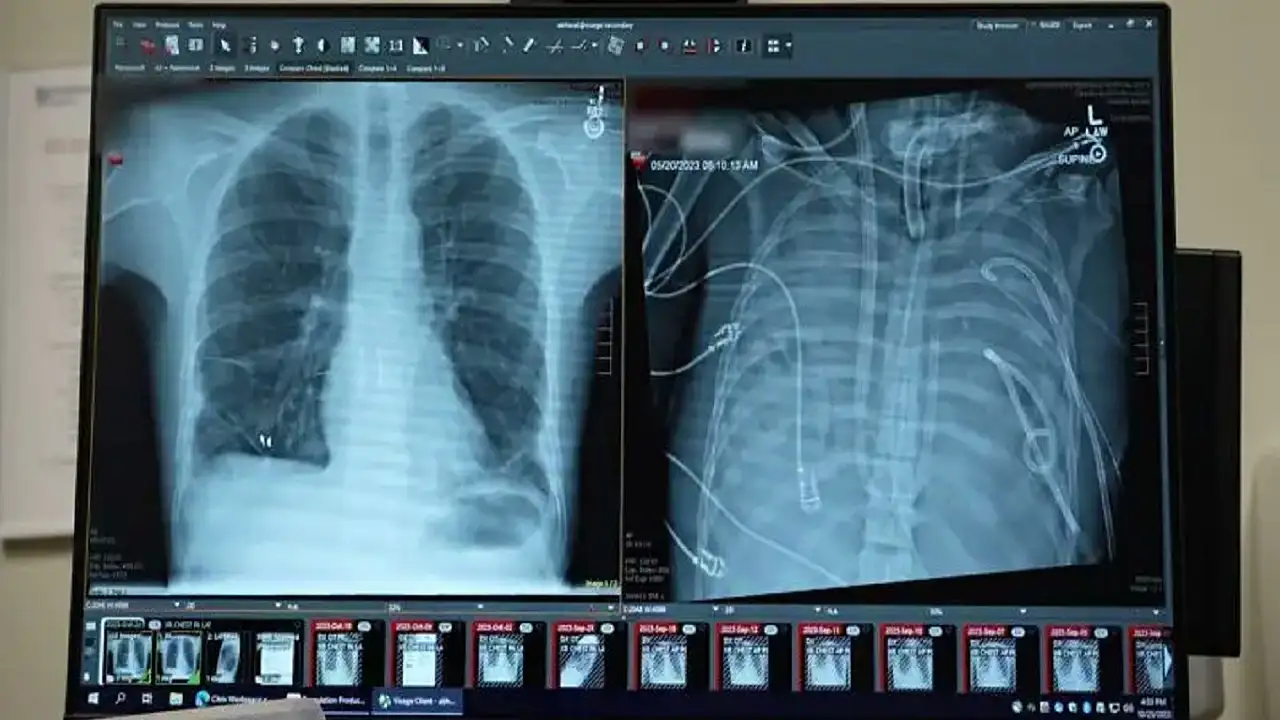

Bunun üzerine cerrahlar, hastanın hastalıklı akciğerlerini tamamen çıkararak geliştirdikleri yapay akciğer sistemine bağladı. Sistem, kalbin sağ tarafından alınan kanı bir pompadan geçirerek oksijen ekliyor ve karbondioksiti uzaklaştırıyor, ardından kanı kalbin sol tarafına yönlendirerek vücuda pompalanmasını sağlıyor. Böylece hem kalbin normal işlevi korunuyor hem de dokulara oksijen ulaştırılıyor.

Daha önce doktorlar, ekstrakorporeal membran oksijenasyonu (ECMO) adı verilen dış destek sistemini kullanarak, nakil bekleyen bazı hastaları akciğersiz olarak hayatta tutmuştu. Ancak Bharat, ECMO’nun kalp için yeterli kan akışını sağlamadığı için gerçek anlamda bir yapay akciğer olmadığını ifade etti.